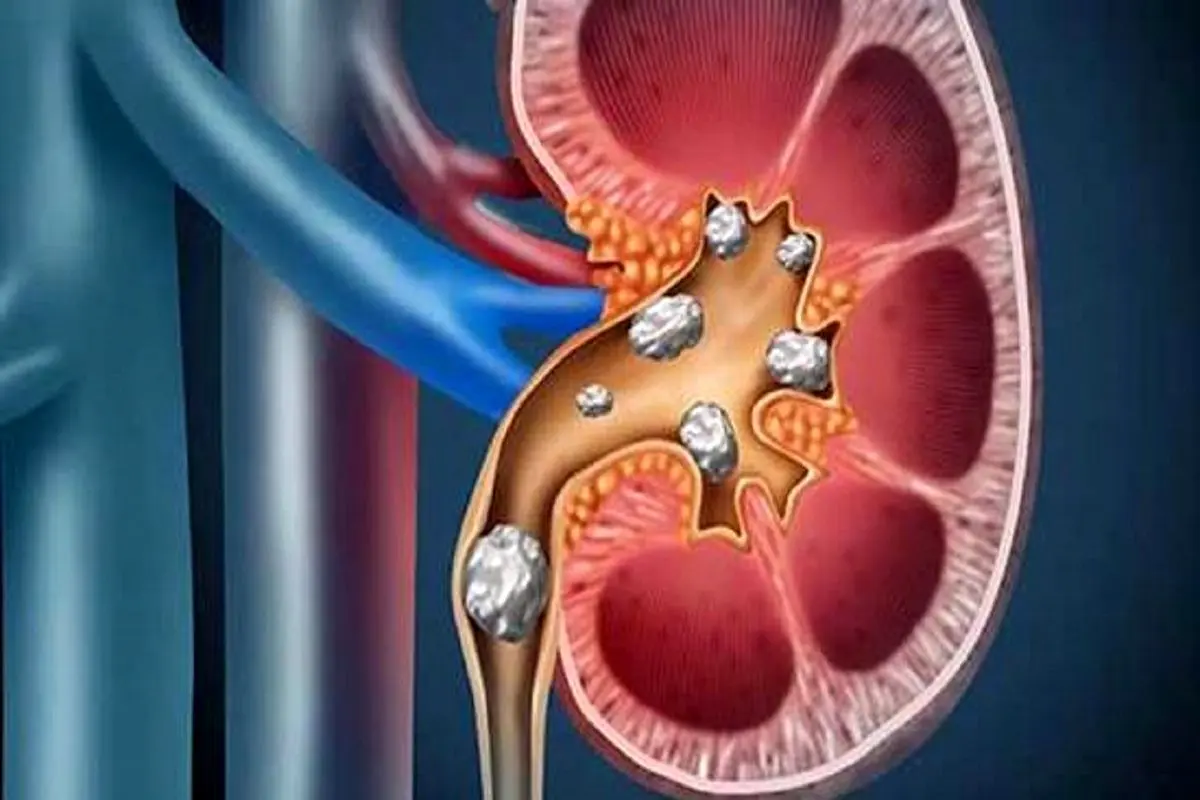

سنگهای کلیه کریستالهایی هستند که هنگام جمع شدن مواد زائد در خون در کلیهها تشکیل میشوند. بعضی از افراد این علائم را بدون هیچ ناراحتی تجربه میکنند، اما اگر سنگها در کلیه یا حالب گیر کنند، لوله کوچکی که به هم متصل میشود، میتواند باعث درد شدید شکم، کلیه یا مثانه شود.

در این مطالعه، ۱۹ نفر تحت تکنیک جدید BWL قرار گرفتند، که در آن ۲۵ سنگ در حداکثر ۱۰ دقیقه شکسته شد و حدود ۹۰ درصد از اندازه سنگ تکه تکه شد، تا ۱۲ میلی متر تا کمتر از ۲ میلی متر. تکنیک SWL، معمولاً حدود ۶۰ درصد سنگها را به اندازه کمتر از ۴ میلیمتر تکه تکه میکند و معمولاً میتوان قطعهای به قطر ۴ میلیمتر را جدا کرد اما دردناکتر از سنگهای کوچک.